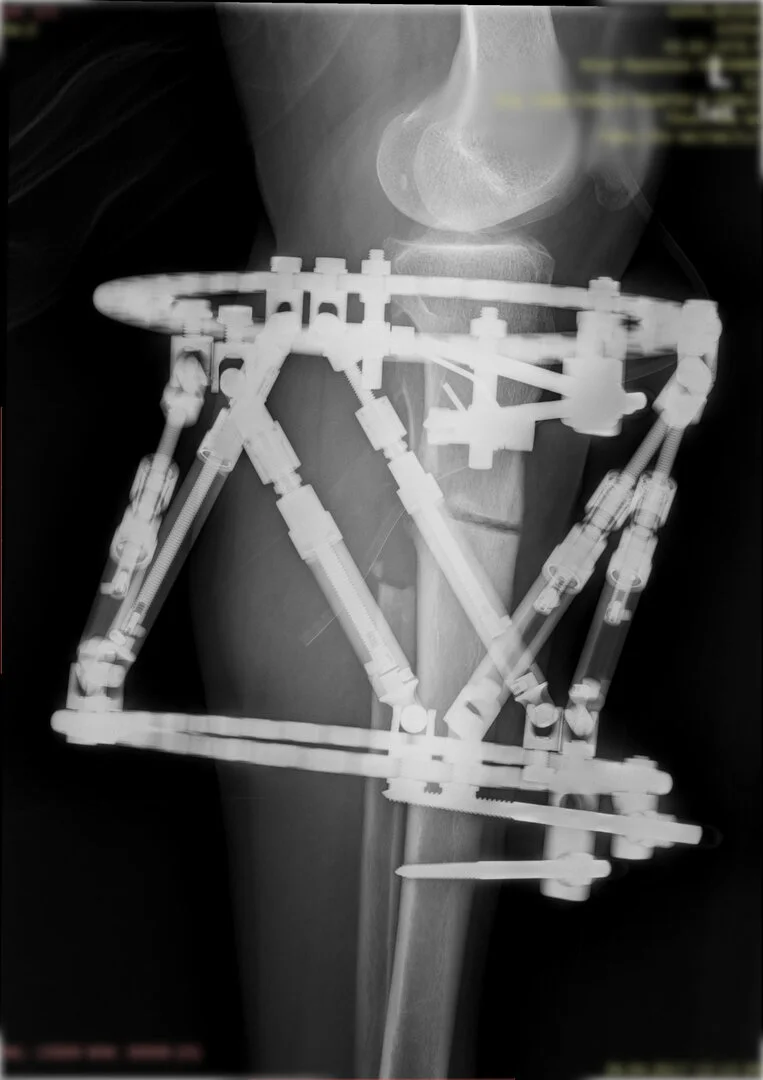

Deformitenin yeri ve miktarına bağlı olarak bilgisayar destekli sirküler eksternal fiksatör ile tedrici düzeltme yapılabilir. Bu sistemin avantajı düzeltme esnasında sistemle oynayarak yeni düzenlemeler yapmanıza izin vermesidir.

Bu ameliyat öncesi bir deformite analizi yapılıp hangi kemikte, normalden ne kadar sapma olduğu tespit edilir. Daha sonra bu kemiğe yine ostetomi yapılarak bu anormal sapma düzeltilir.  Bu düzeltme plak-vida veya intramedüller çivi ile akut olarak düzeltilebileceği gibi bilgisayar destekli sirküler eksternal fiksatör ile tedrici olarak ta yapılabilir. Hangi yöntemin hangi hasta için uygun olacağına hasta özelinde karar veriyoruz, ne tür cerrahi tedavi olması gerektiğini danışabilirsiniz.

Görüntüleri büyütmek için üzerine tıklayınız.